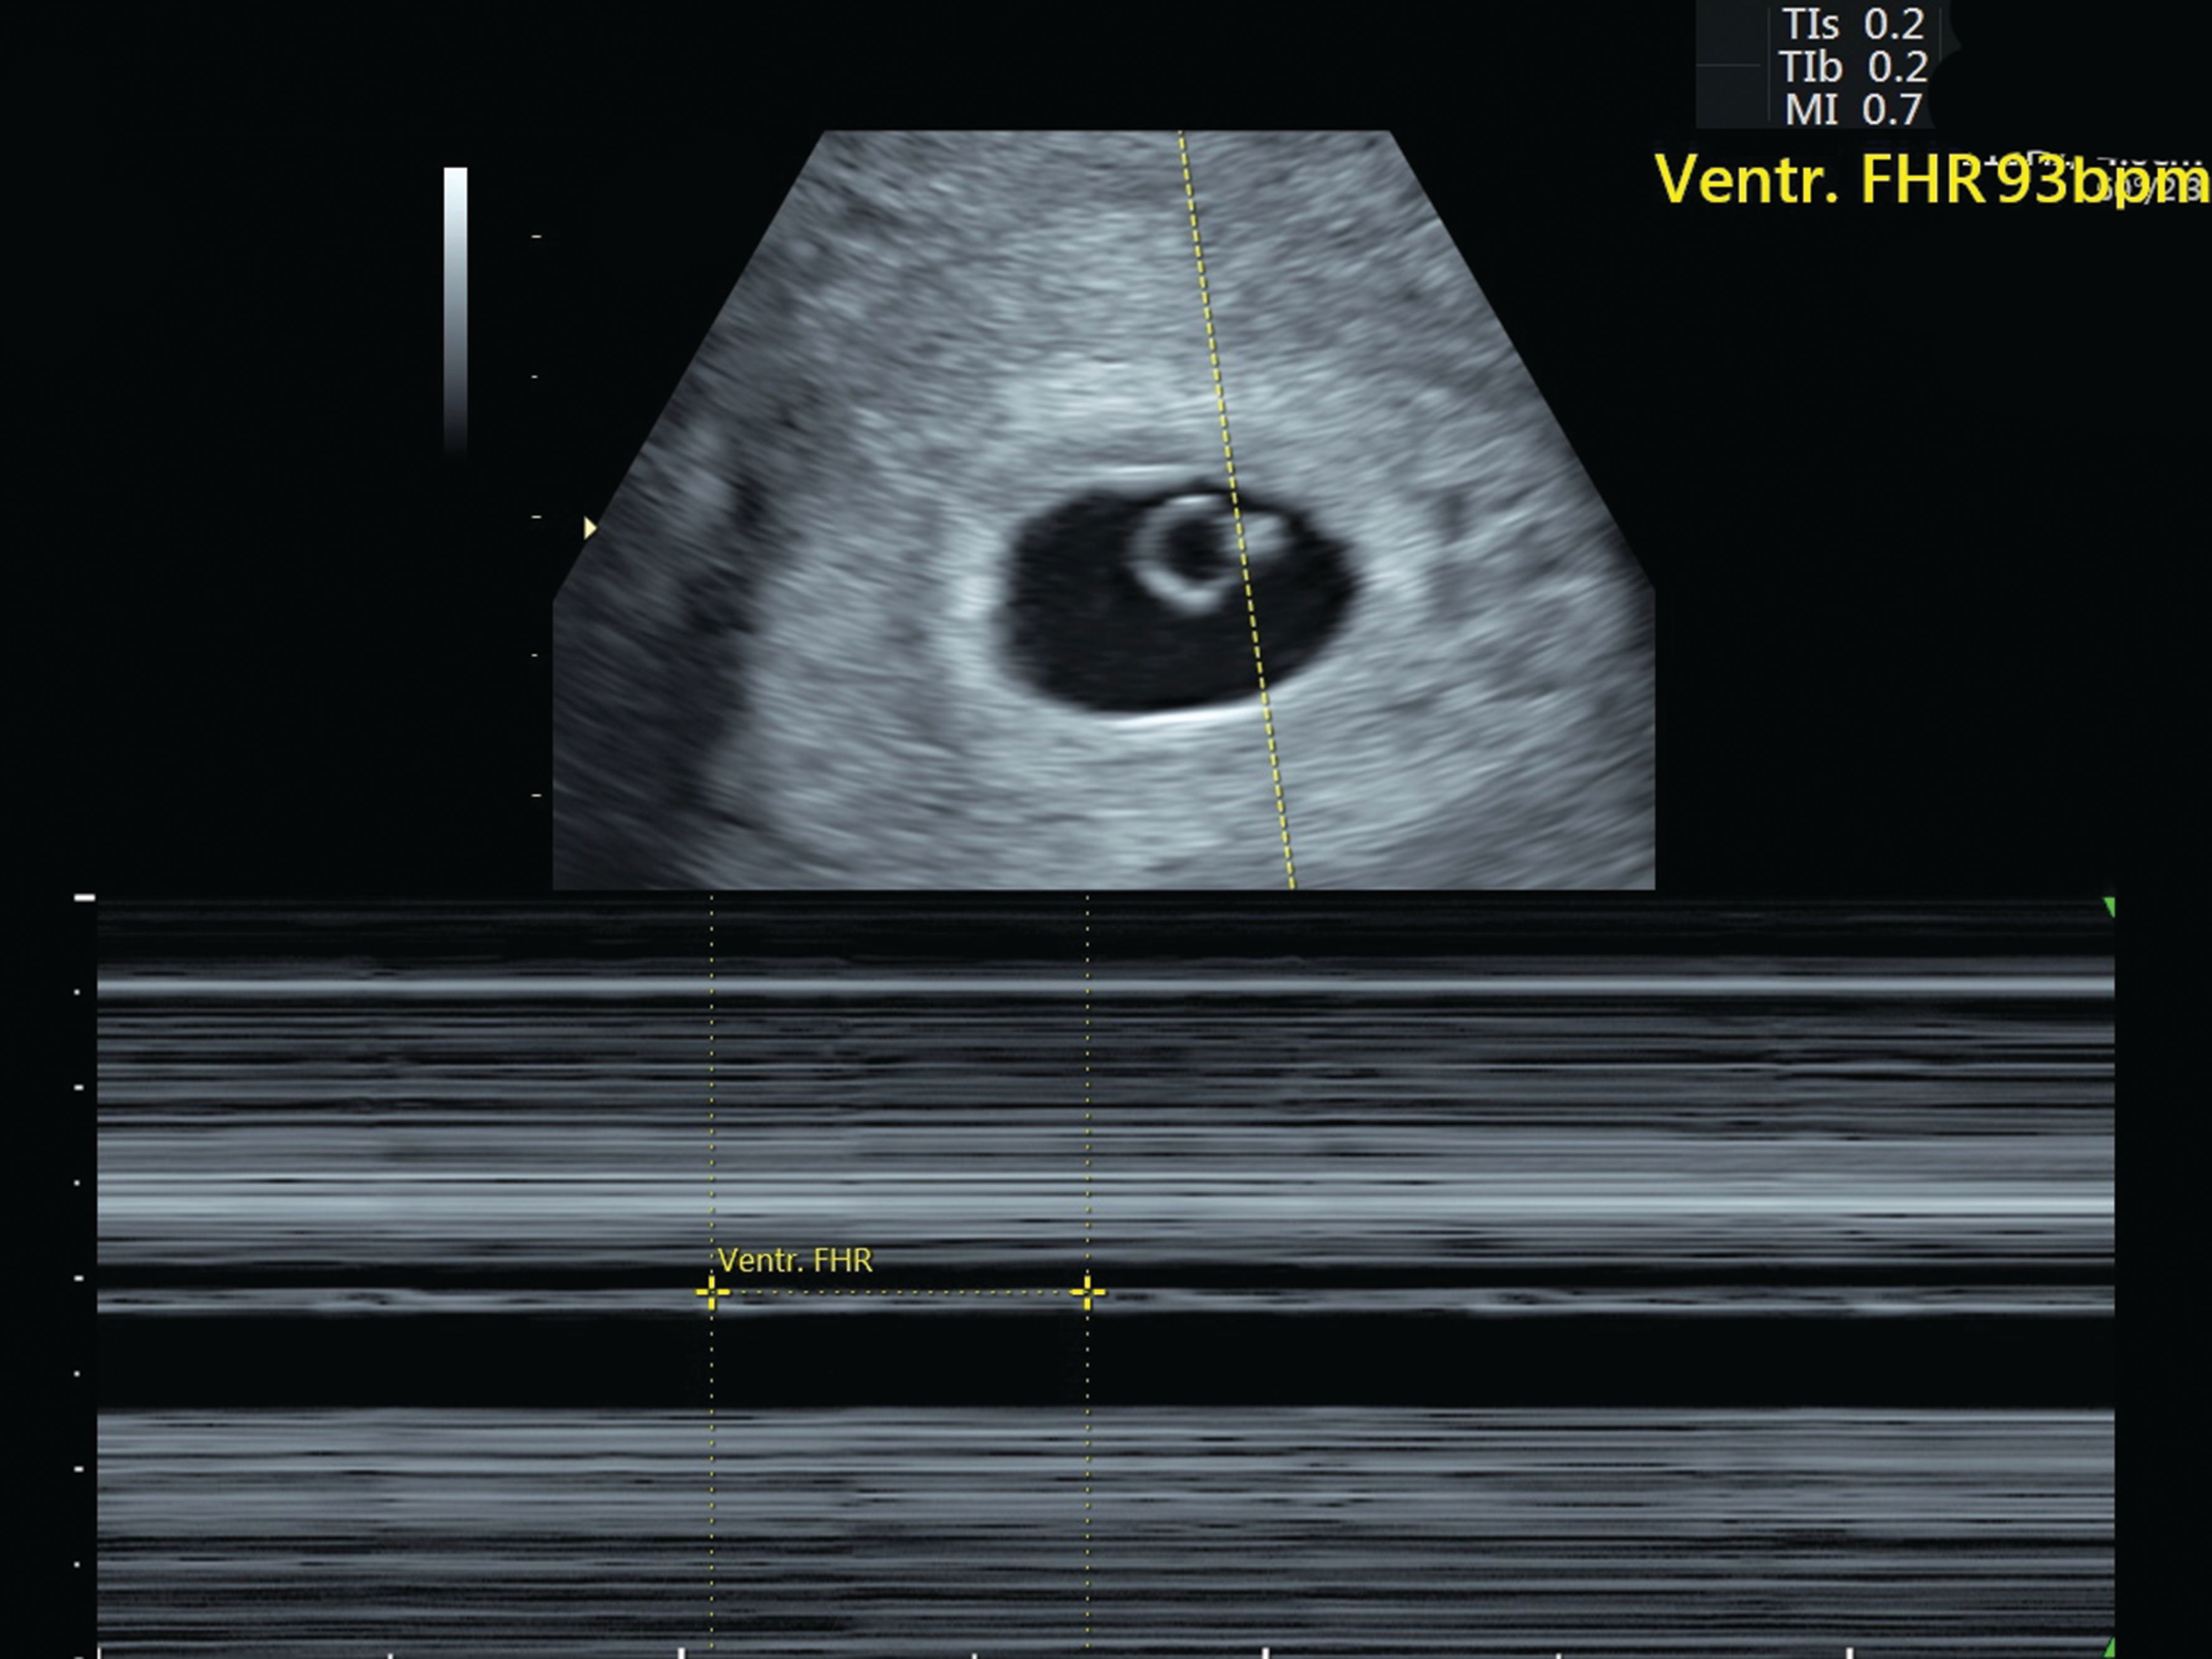

Like most expectant parents they couldnt wait to see the first glimpse of their little one. The risk of miscarriage at six weeks gestation is also based on the heart rate noted on ultrasound.

Your doctor wants to know if its high in. Often seeing no yolk sac or a yolk sac that is smaller than normal or otherwise misshapen at 6 weeks can be a sign of miscarriage. Risk of Miscarriage according to Fetal Heart Rate.

The mere presence of a fetal heart rate is. Usually the physical process of a. Essentially the short answer is no.

An abdominal ultrasound can detect a heartbeat at 6 to 8 weeks time. Falling levels of hCG human. Ultrasound scans can detect a fetal heartbeat at approximately 6-7.